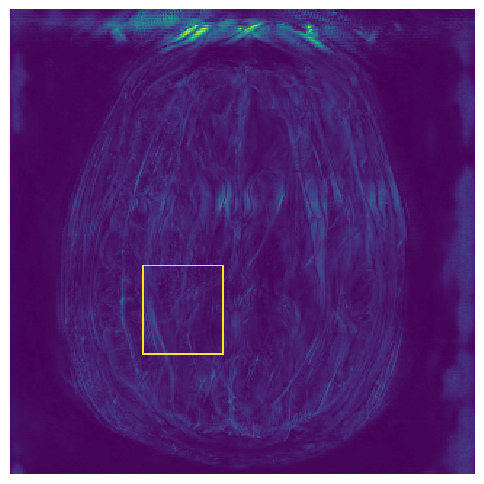

(e) NPB-REC Std.

Figure 3: Reconstructions results. Rows 1 and 3: Examples of comparing the ground truth (GT) fully sampled image to the reconstructed images obtained by the three models (1-3), NPB-REC, baseline, E2E-VarNet trained with Dropout, and the NPB-REC std. map at accelerations R=4𝑅4R=4, R=8𝑅8R=8, respectively. Rows 2 and 4: The corresponding annotated ROIS of Nonspecific white matter lesions.

Fig. 3 presents examples of reconstruction results obtained by (1) our NPB-REC approach, (2) the baseline, and (3) Monte Carlo Dropout, for equispaced masks with two different acceleration rates R=4𝑅4R=4 and R=8𝑅8R=8. The reconstructed images predicted by the three models are smoother than the reference image. This is due to the fact that all the models were trained with SSIM loss, which tends to produce overly smooth reconstructions while preserving the diagnostic content and the anatomical features Sriram et al. (2020a). These images can be enhanced by dithering the image by adding a small amount of random Gaussian noise to produce a more textured reconstruction, as proposed in Sriram et al. (2020b).

Table 1 presents the mean PSNR and SSIM metrics, calculated over the whole inference set, for the three models. Our NPB-REC approach achieved significant improvements over the other methods in terms of PSNR and SSIM (Wilcoxon signed-rank test, pmuch-less-than\ll1e-4, except for SSIM values in line W, R=4𝑅4R=4 where they are roughly the same for NPB-REC and Baseline). The improvement in the reconstruction performance can be noted both quantitatively from the metrics, especially for masks with acceleration rate R=8𝑅8R=8, and qualitatively via the images of annotations, where our results show less smoothness than those obtained by Dropout.